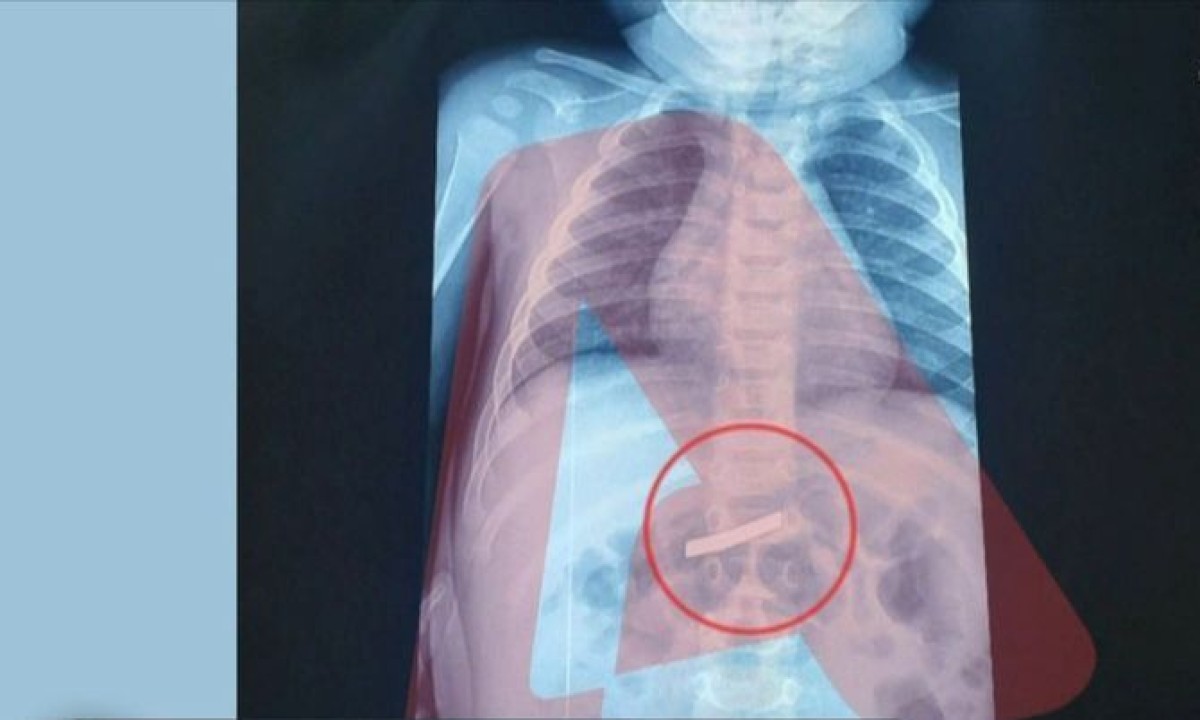

Σε νοσοκομείο Παίδων της Αθήνας μεταφέρθηκε εσπευσμένα ένα αγοράκι μόλις τριών ετών, το οποίο κατάπιε ένα ξυραφάκι.

Άμεσα το παιδί υποβλήθηκε σε ακτινογραφία, η οποία έδειξε ότι όντως υπήρχε ένα ξυραφάκι στο στομάχι του παιδιού, όπως είχαν ενημερώσει τους γιατρούς οι γονείς του, ενώ προσδιορίστηκε και το ακριβές σημείο, ώστε οι χειρουργοί να προχωρήσουν σε επέμβαση αφαίρεσής του με ασφάλεια και ακρίβεια.

Η έκβαση της επέμβασης ήταν επιτυχής και το μικρό παιδί αναρρώνει.